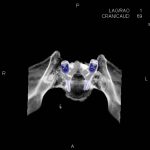

- Diagnosticul traumatismelor de bază de craniu

- Complexe cranio-sinusale

- Complexe cranio-etmoidale

- Complexe cranio-orbitare

- Complexe cranio-faciale